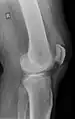

| An x-ray demonstrating quadriceps tendon rupture. Note the abnormal angle of the patella and soft-tissue swelling marked by the arrow. | |